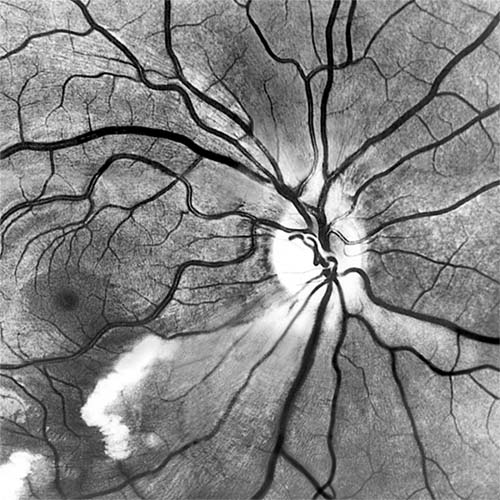

In anterior segment ischemia, patients develop iritis, intraocular pressure changes, and pupillary abnormalities. In retinal ischemia (Figure 15-12A), patients show evidence of capillary dilation and hemorrhages, capillary occlusion, new vessels at the optic disk, and cotton-wool spots.

Figure 15-12

Figure 15-12: A: Fluorescein angiogram of left fundus in a patient with chronic ocular ischemia secondary to Takayasu's disease. Note capillary dilation, leakage of dye, retinal hemorrhages, cotton-wool spots, and neovascularization of the optic nerve head. B: Fluorescein angiogram, showing leakage at optic disk and macula in a patient with chronic ocular ischemia secondary to dural arteriovenous fistula.

Carotid Cavernous Fistula

Carotid cavernous fistula results from a communication between the carotid artery or its branches and the cavernous sinus, producing characteristic vascular signs. Direct carotid fistulas are usually acute, florid, and posttraumatic, whereas fistulas from dural vessels are usually chronic, mild, and not associated with trauma. Clinical features include elevated intraocular pressure, dilated conjunctival vessels, dilated retinal vessels with hemorrhages and fluorescein leakage (Figure 15-12B), ophthalmoplegia (usually lateral rectus), and bruit. computed tomography (CT) and magnetic resonance imaging (MRI) show thickened ocular muscles and a dilated superior ophthalmic vein. The condition must be differentiated from thyroid eye disease, and interventional radiology is the ultimate diagnostic and therapeutic resource.